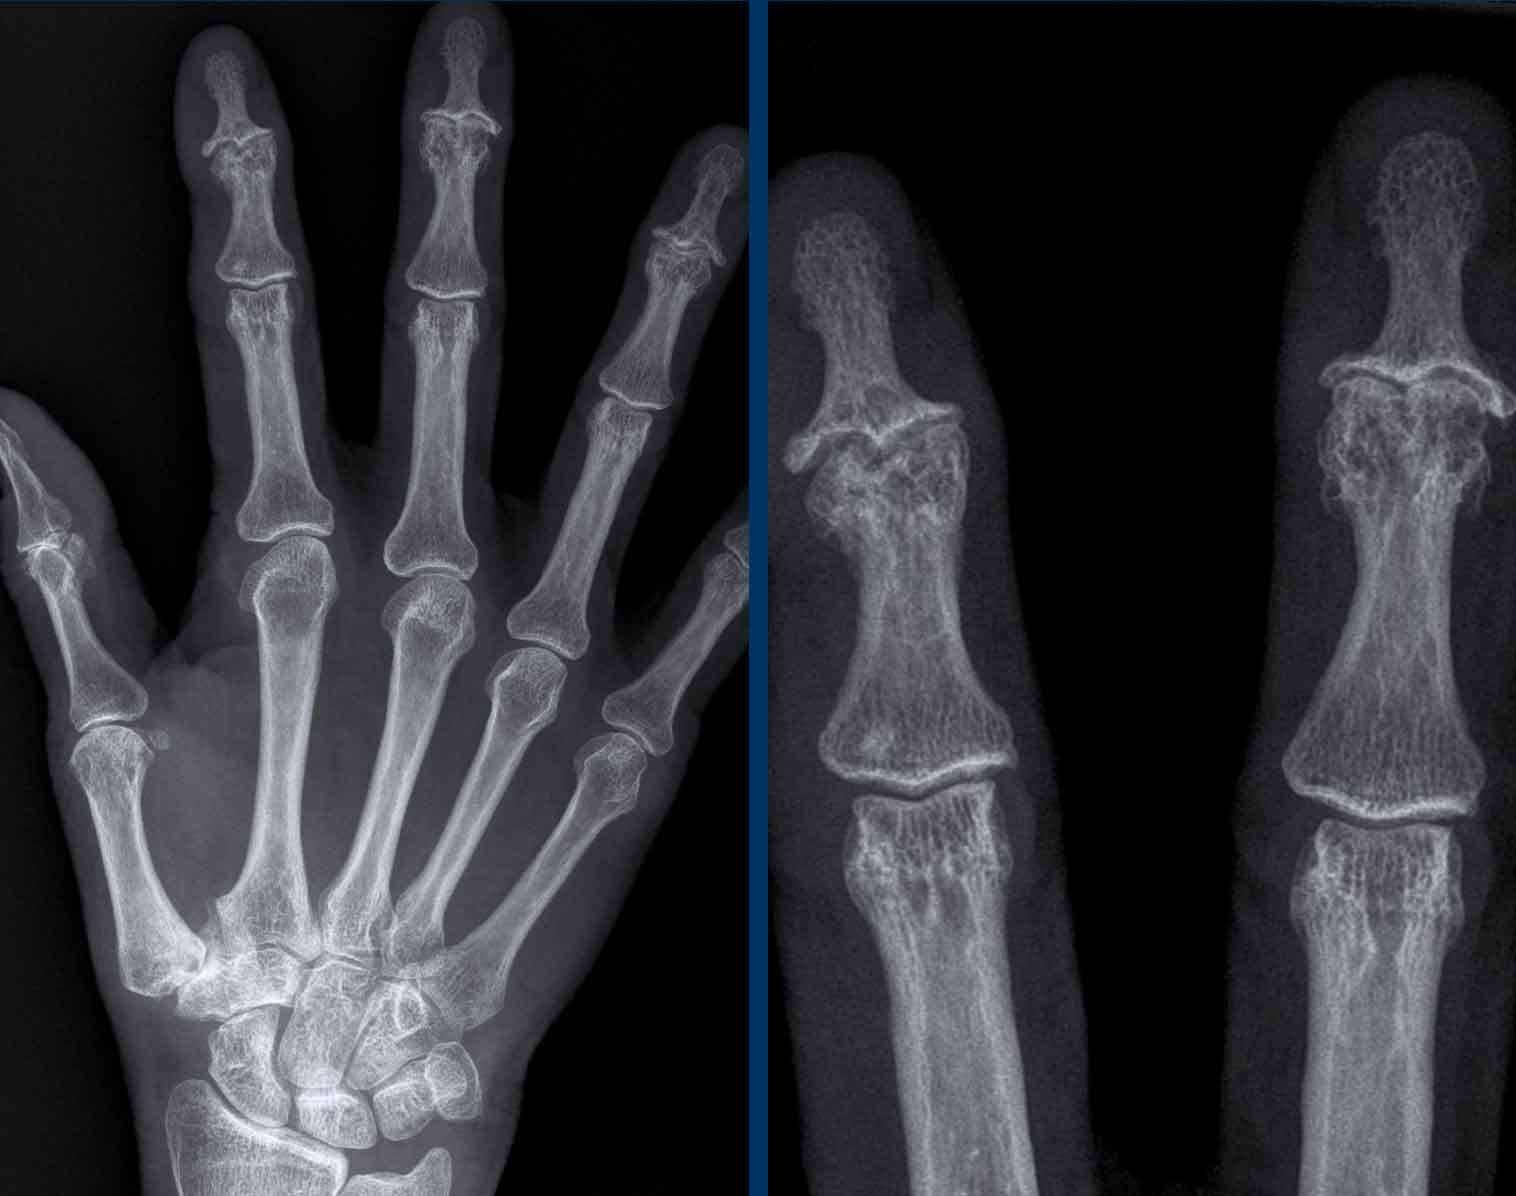

Gout Hand Radiograph · RheumTutor Gout Dip Joint Xray Chronic gout is associated with changes in. Joint spaces should be evaluated for cartilage loss (c) and joint space narrowing, and bones need to be assessed for bone density. Dip gouty tophi can often be treated by aspiration and manual expression of tophaceous material. The dip joint of the right index finger is affected by juxta articular erosion. Arthrodesis may. Gout Dip Joint Xray.

e Single anteroposterior radiograph of the hand shows multiple Gout Dip Joint Xray The dip joint of the right index finger is affected by juxta articular erosion. Dip gouty tophi can often be treated by aspiration and manual expression of tophaceous material. Imaging is a helpful tool for clinicians to evaluate diseases that induce chronic joint inflammation. Joint spaces should be evaluated for cartilage loss (c) and joint space narrowing, and bones need. Gout Dip Joint Xray.